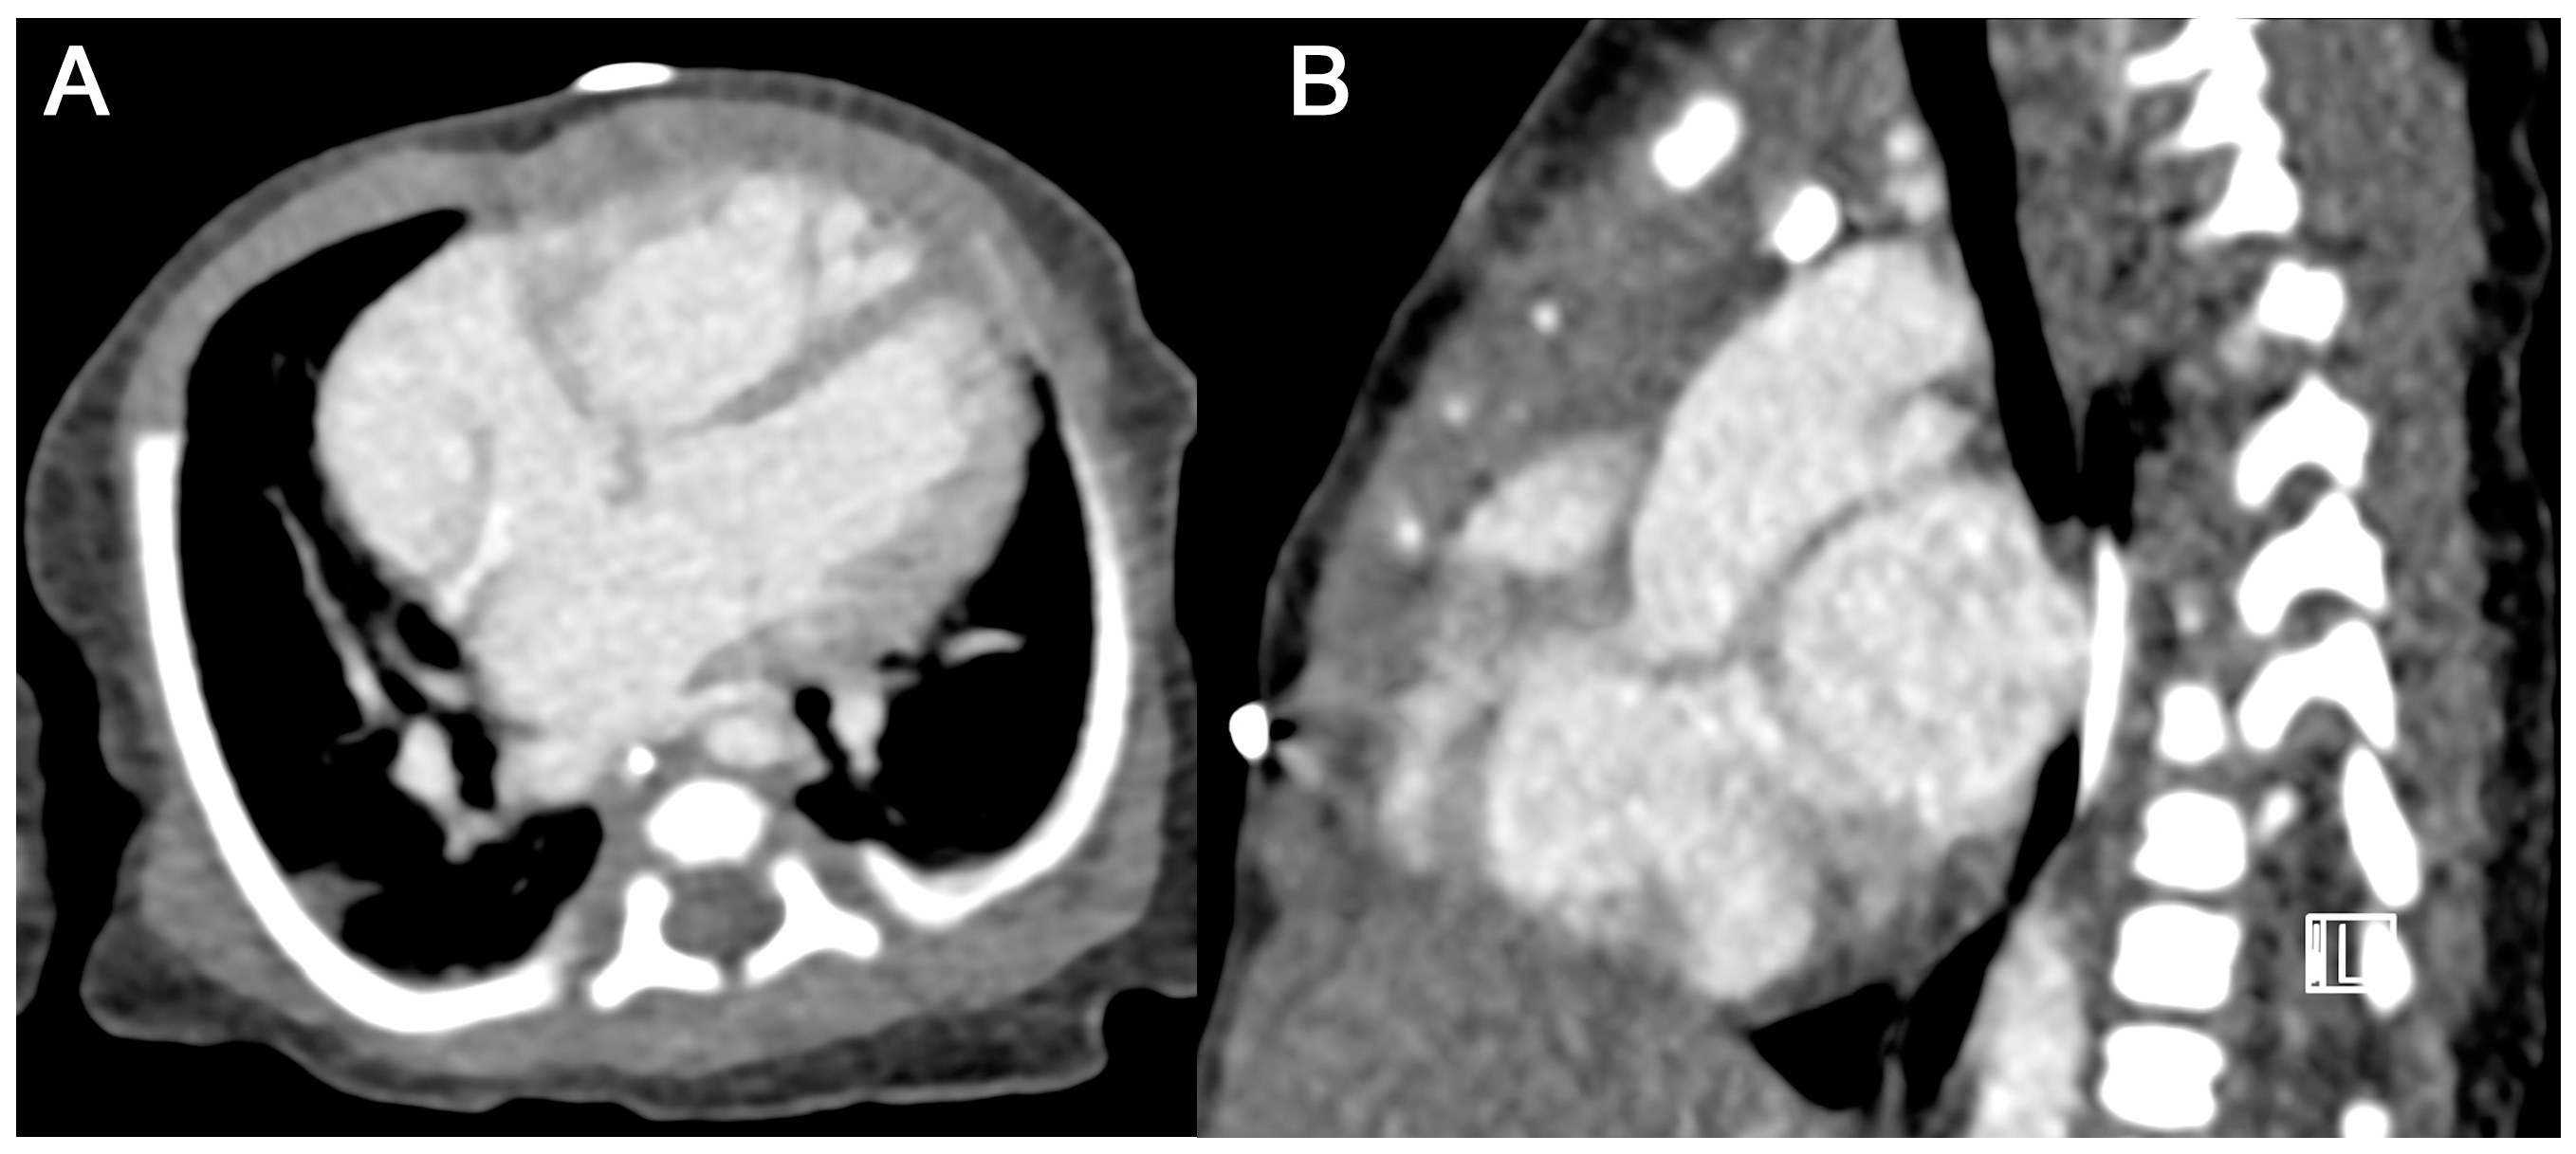

3.3.2. Subjective Image Quality